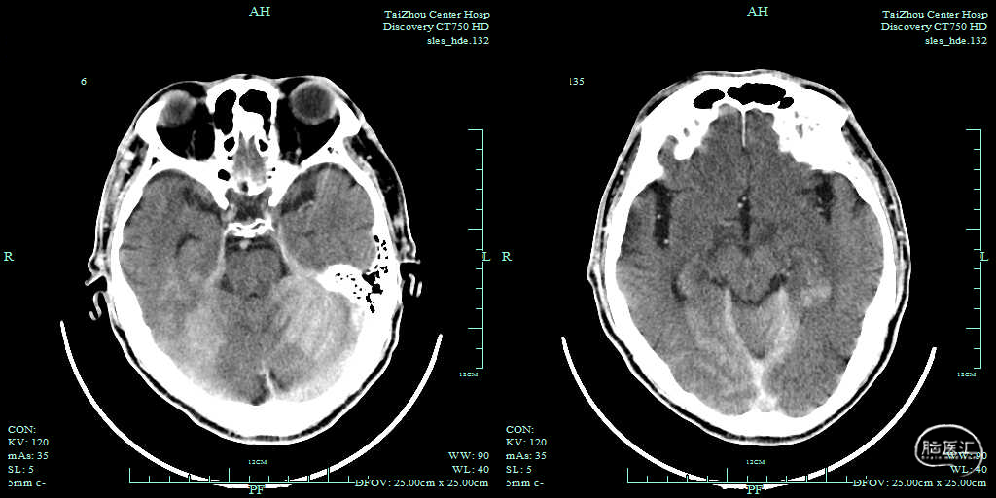

术后即刻头颅CT

术后6h头颅CT